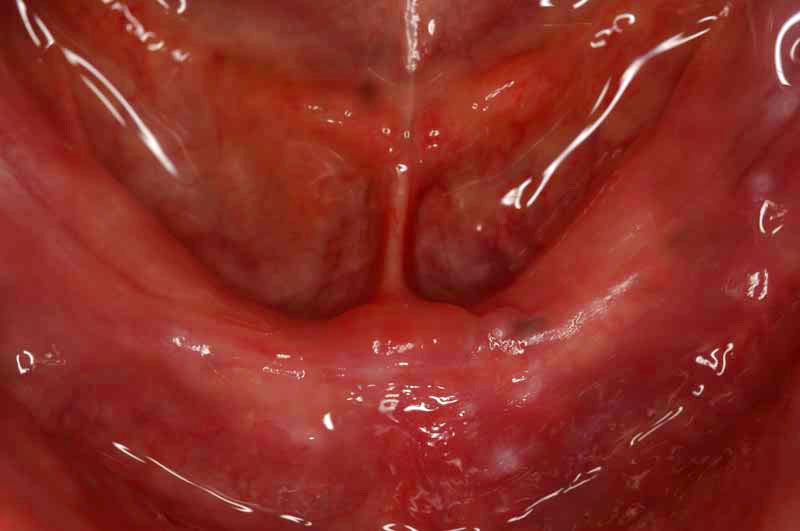

CASE 1 歯の全くない方

歯の全くない方の場合、インプラントを4本いれるとブリッジでつなげて自分の歯のようにすることが可能です。または2本いれて磁石の力で従来の総入れ歯を吸い付かせる方法も可能です。